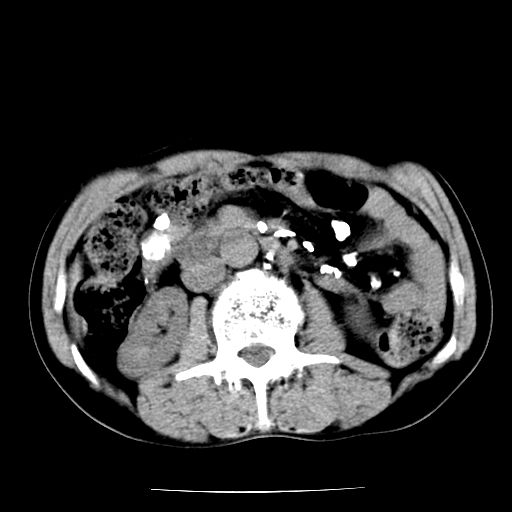

男,59岁,“结核性胸膜炎”30余年,胸部经常疼痛,多次x检查提示“肺部”炎症。腹部疼痛5日,b超提示:“肝内短管结石,余显示不清,建议进一步检查。”

两肺结核并右侧胸腔积液;脾脏、腹腔及腹膜后淋巴结结核[陈旧性];肝内胆管结石

胸部腹部都是结核(双肺。纵隔淋巴结,肝脏,脾脏,肠系膜)

两肺结核并右侧胸腔积液;脾脏、腹腔及腹膜后淋巴结结核[陈旧性];肝内胆管结石。直肠息肉?